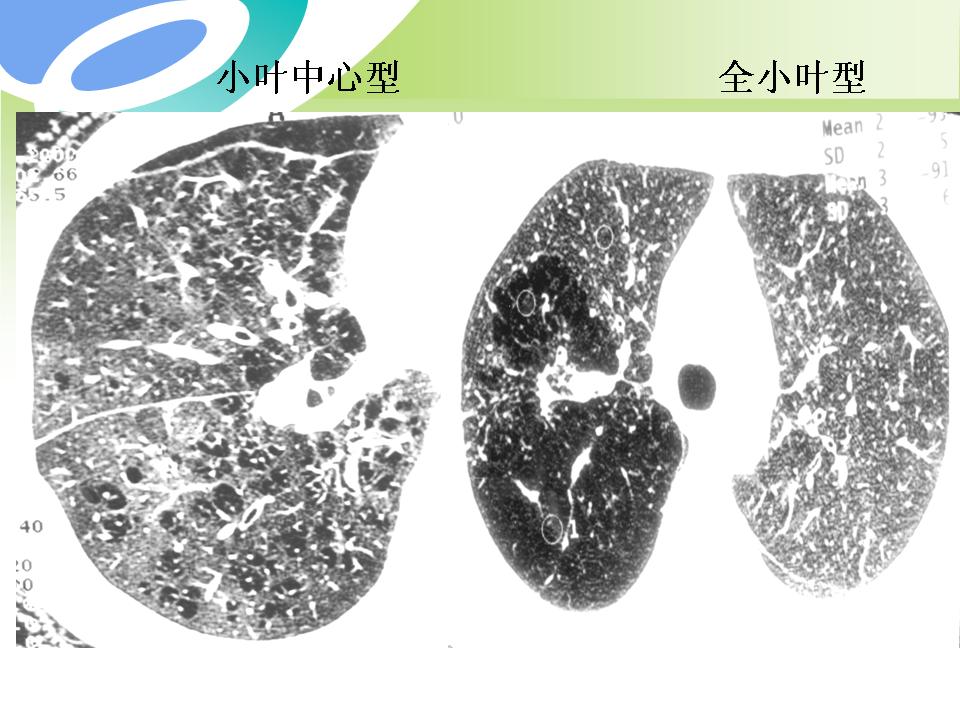

肺部病变的CT基本征象